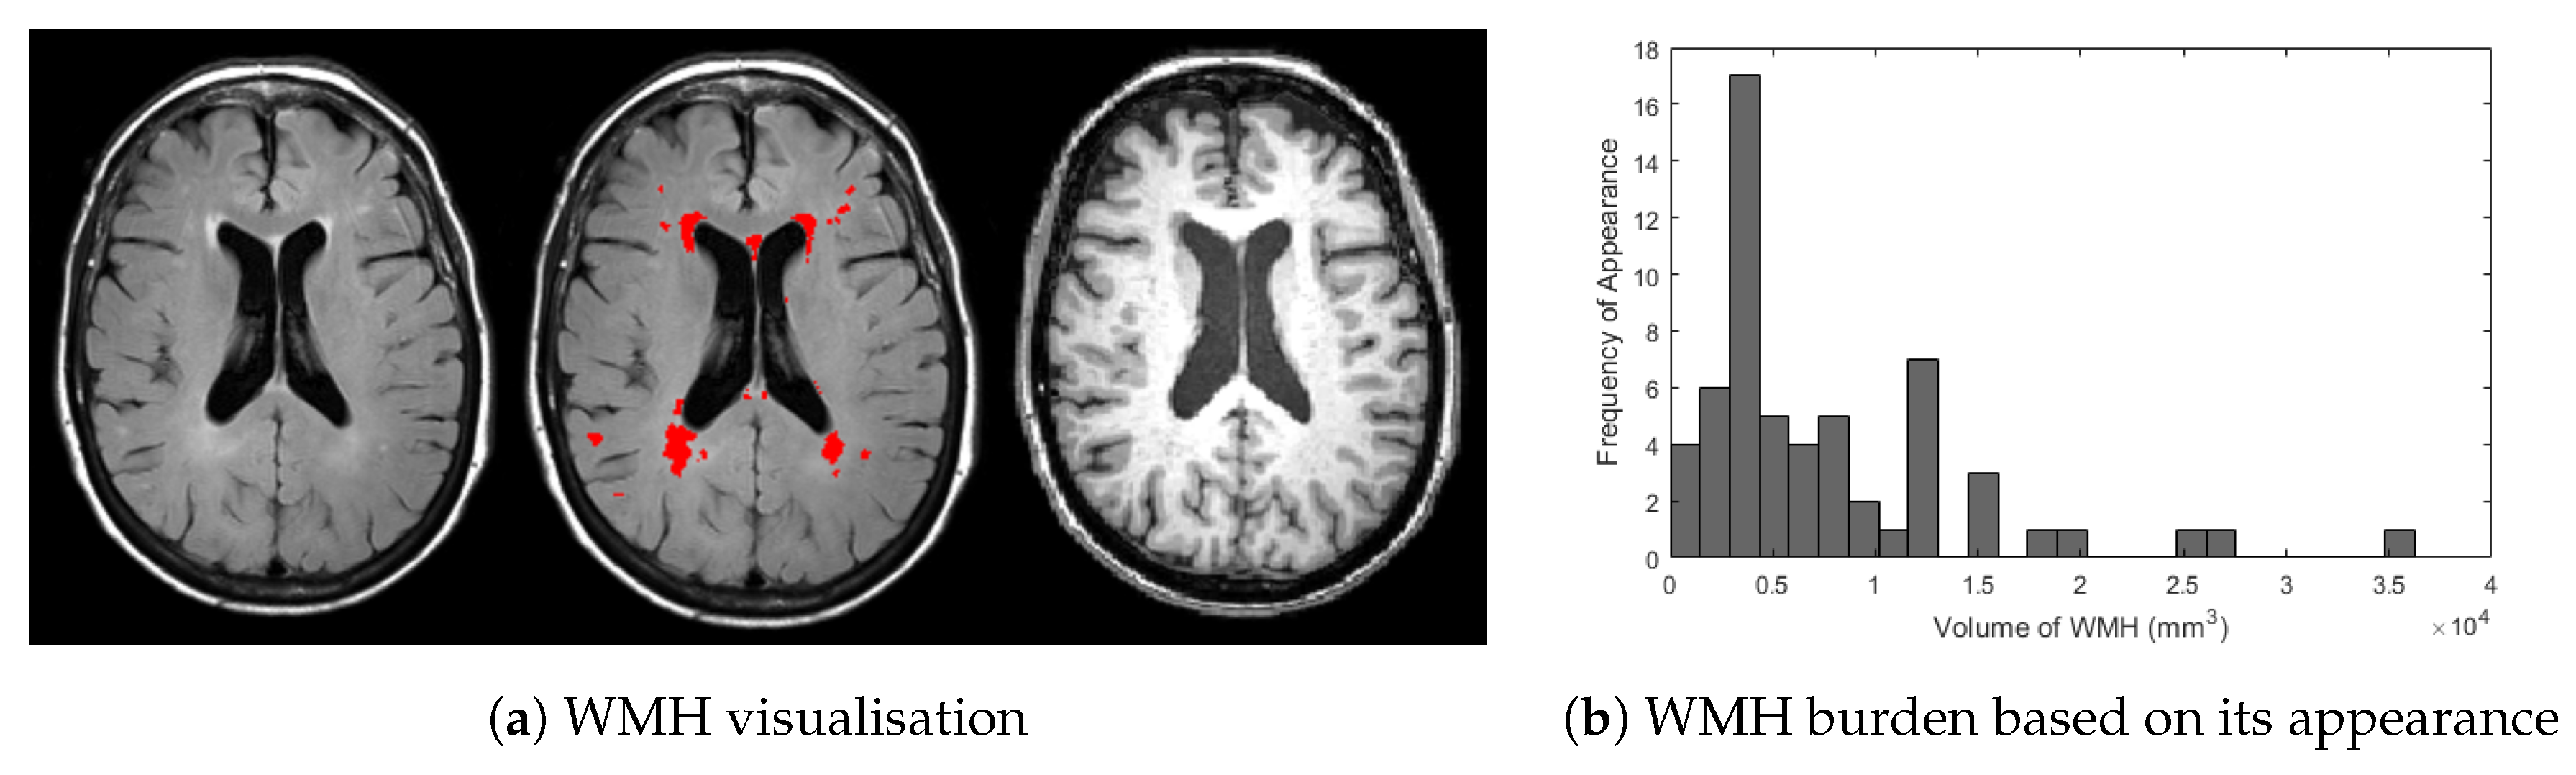

White matter hyperintensities (WMH) are brain regions that exhibit intensity levels higher than those of normal tissues on T2-weighted magnetic resonance images (MRI). These regions are important in brain image analysis because they have been reported to be associated with a number of neurological disorders and psychiatric illnesses such as dementia and Alzheimer’s Disease (AD), including its progression [1,2]. While WMH appear as bright regions (i.e., hyperintensities) in T2-weighted MRI, they appear as dark regions (i.e., hypointensities) in T1-weighted MRI. Visual examples of WMH in T2-based-fluid attenuated inversion recovery (T2-FLAIR) and T1-weighted of MRI can be observed in Figure 1a.

Figure 1.

(a) Visualisation of WMH in T2-FLAIR (left) and T1-weighted (right) of MRI and (b) histogram frequency of appearance based on WMH burden from ADNI dataset used in this study. In (a) above, bright regions of WMH are overlaid by red masks marked by clinical observer (centre). Whereas, histogram in (b) were produced by calculating WMH volume for all 60 MRI data from ADNI dataset used in this study.

A challenge always faced in WMH segmentation is the inaccuracy of machine learning algorithms in detecting early stages of brain pathology. WMH at early stages are difficult to assess for two main reasons. One is their subtlety, which makes WMH hard to identify even by human eyes and easily mistaken as imaging artefacts [11]. Another is their small volume as depicted in Figure 1b. These two facts make the development of automatic WMH segmentations for brains with mild or no vascular pathology challenging [10].